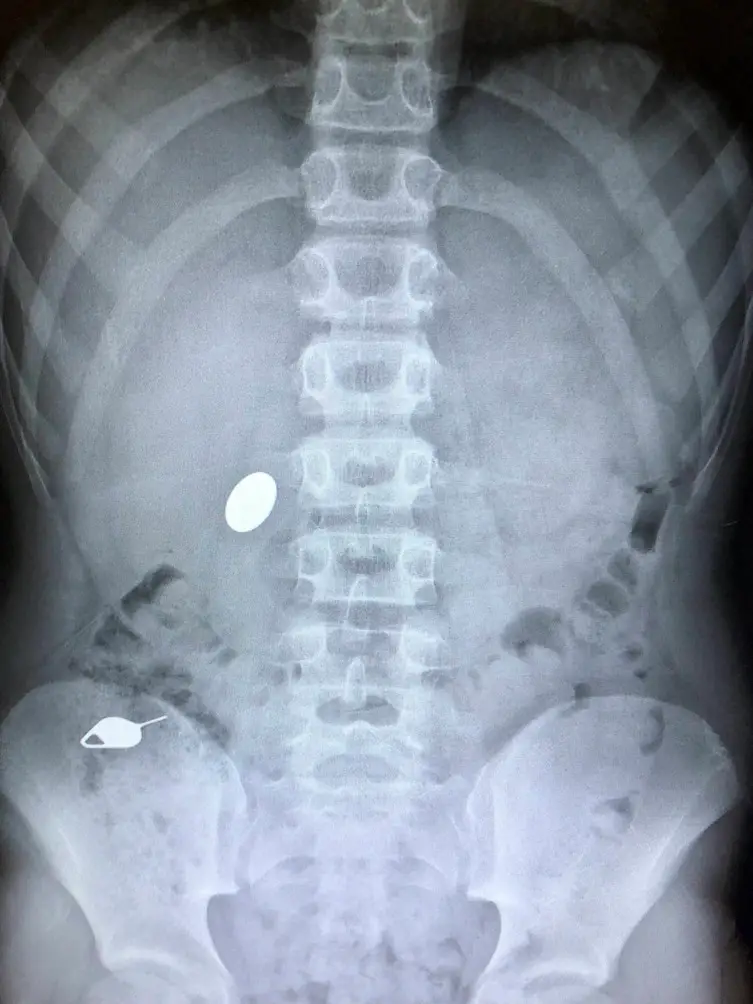

| Imágenes que podemos disfrutar gracias a la ciencia (10 puntos) Posted: 21 Feb 2018 12:29 PM PST Esta es una colección variada de inventos e imágenes curiosas que no hubiesen sido posibles, si no fuera por los avances científicos. 1. Así lucen las Papilas Orales de un ciervo. 2. Este es el daño que hace una onza de plástico que impacta un bloque de aluminio a 24000kmh.Anuncios 3. Una mujer sostiene una prótesis de mandíbula inferior impresa en una impresora 3D. El costo es menor y se encaja perfectamente a la medida del paciente.Anuncios 4. Esto es lo que sucede cuando pasas electricidad a un cubo acrílico. Las figuras de Lichtenberg quedan para siempre. 5. También son figuras de Lichtenberg provocadas por el tendido eléctrico. 6. Los peces sálpidos o transparentes por lo general son inofensivos, "no muerden" ni atacan a los humanos. Es algo que no se ve todos los días. 7. Estas no son rocas. Son plantas llamadas "Lithops" o "Piedras Vivas" que desarrollaron un camuflaje impresionante.Anuncios 8. Este es un sorprendente método de seguridad que se puede encontrar en el dinero Canadiense. 9. Los Optometristas a veces te tiñen los ojos para revisar si no tienes daño de córnea. El material hace que tus ojos brillen en la oscuridad. 10. Esto fue lo que se recolectó después de usar una secadora de manos de aire caliente en un baño público. 11. Este símbolo olímpico fue hecho enteramente con drones, para la inauguración de los Juegos de Invierno 2018.Anuncios 12. Así luce el caparazón de un caracol visto en un microscopio. 13. Así es como pestañean las gallinas. Tienen una membrana parecida a un párpado que les recubre el ojo. 14. Un padre muestra la radiografía de su hijo después de haberse tragado una moneda y una herramienta para sacar tarjetas SIM de un teléfono. 15. Así luce una aguja de una jeringa, luego de haberse colocado la inyección. 16. Los cachalotes duermen de forma vertical. 17. Este fue el Quetzalcoatlus northropi, el animal volador más grande que ha existido. |